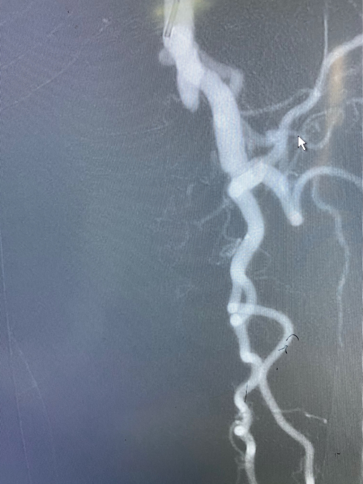

手术过程

图:推送saber球囊

图:开通腘动脉主干

图:4mm/5mm球囊顺序行股腘动脉PTA,3mm球囊行腓动脉PTA

图:由肱动脉先行股动脉支架置入,而后顺行穿刺股总动脉

图:胫腓干夹层,置入3.5mm*35mm药涂支架(冠脉支架)

图:术后造影示股腘动脉、腓动脉及足部动脉显影好